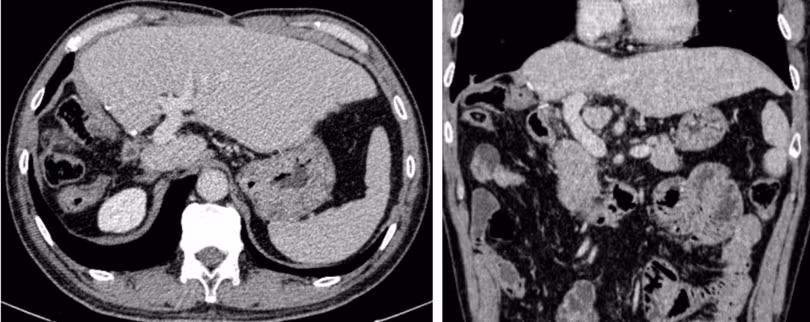

1767430802217.png

Hình ảnh chụp cắt lớp vi tính sau phẫu thuật 4 năm: Gan trái bệnh nhân tốt, tĩnh mạch cửa thông thoáng, không có tái phát tại gan và di căn xa.

Kết quả chụp cắt lớp vi tính cho thấy gan trái còn lại chức năng tốt, tĩnh mạch cửa thông thoáng, không ghi nhận tái phát tại gan cũng như di căn xa.

Kết quả theo dõi sau 4 năm cho thấy chiến lược này đã phát huy hiệu quả rõ rệt, khi bệnh nhân không tái phát tại gan và không có di căn xa. Trong bối cảnh phần lớn bệnh nhân ung thư gan kèm huyết khối tĩnh mạch cửa trên thế giới vẫn chủ yếu được điều trị giảm nhẹ, thì thành công tại BV Việt Đức cho thấy điều trị đa mô thức kết hợp phẫu thuật có thể mở ra cơ hội sống thực sự cho những ca bệnh từng bị coi là vô vọng.